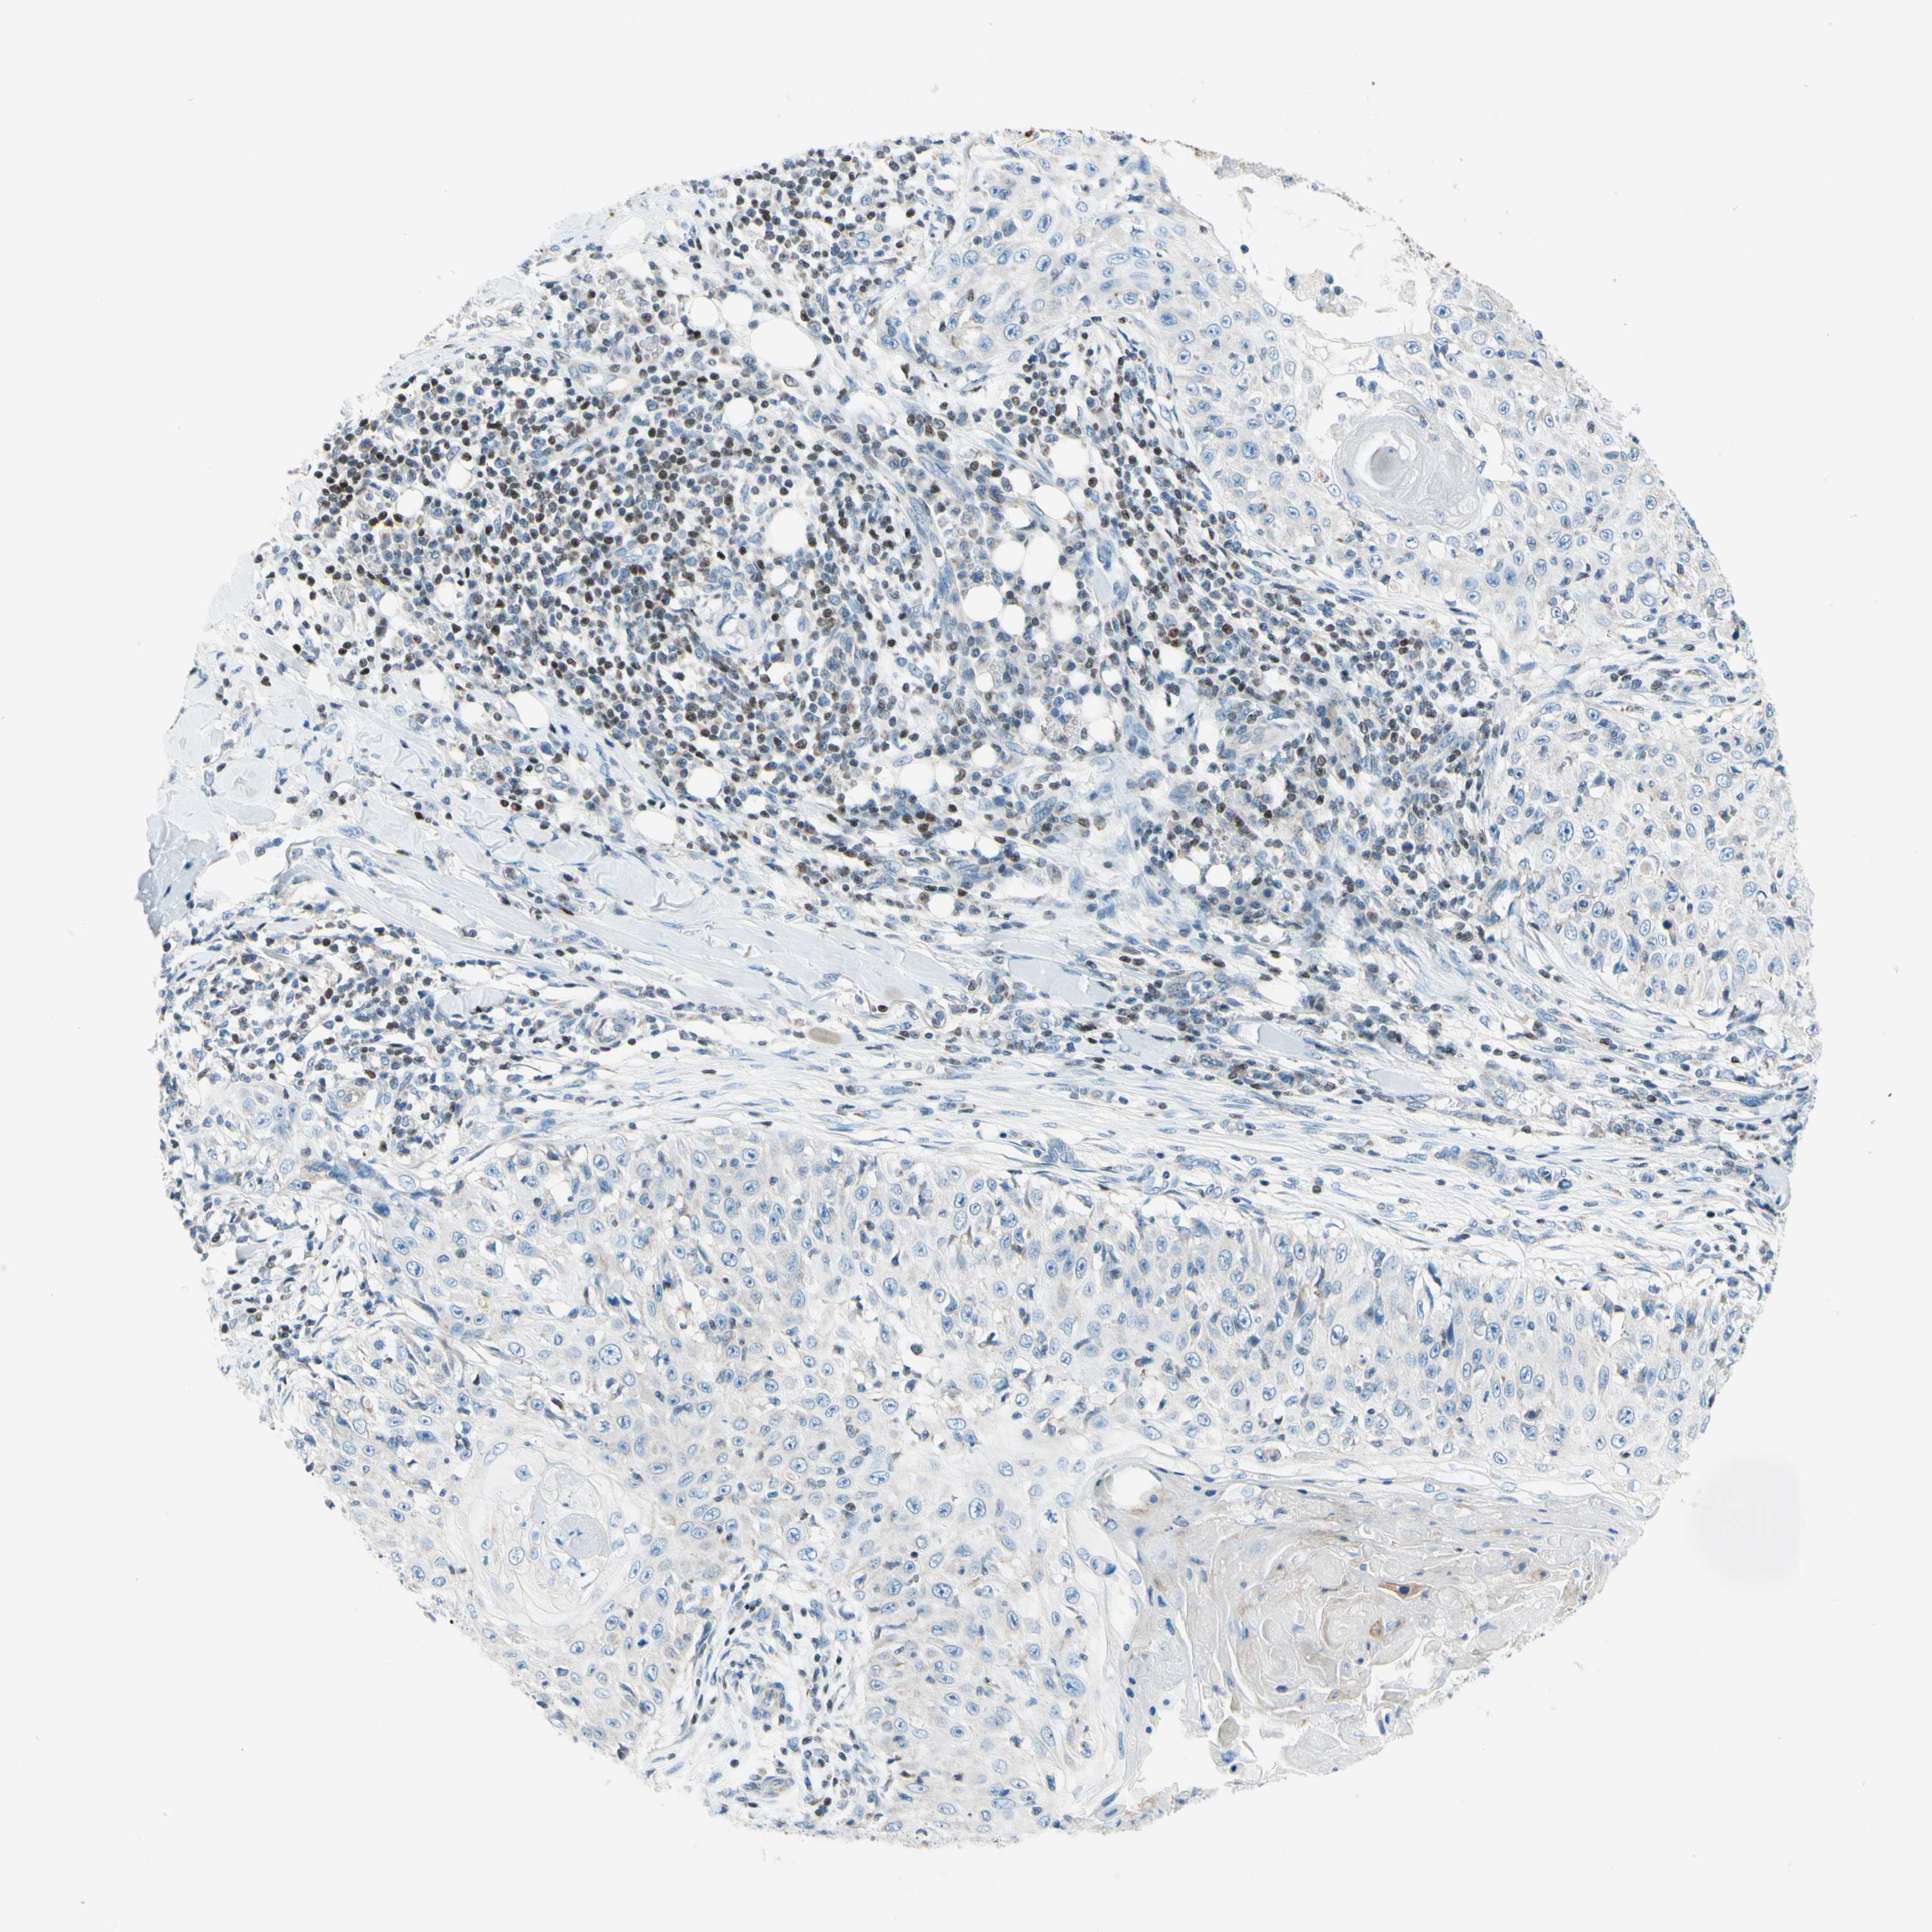

Basal cell and squamous cell cancer

SKIN CANCER - Protein expressioni

A mouse-over function shows sample information and annotation data. Click on an image to view it in a full screen mode. Samples can be filtered based on level of antibody staining by selecting one or several of the following categories: high, medium, low and not detected. The assay and annotation is described here.

Each image is clickable and will lead to virtual microscopy that enables deeper exploration of all samples and also displays staining intensity scores, fraction scores and subcellular localization as well as patient and tissue information for each sample.

Antibody HPA056480

Staining

High

Medium

Low

Not detected

Intensity

Strong

Moderate

Weak

Negative

Quantity

>75%

75%-25%

<25%

None

Location

Nuclear

Cytoplasmic/membranous

Cytoplasmic/membranous,nuclear

Squamous cell carcinoma, NOS